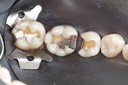

Wayne Chin #2 pre-op

Wayne Chin #2 prep

Wayne Chin #2 finish